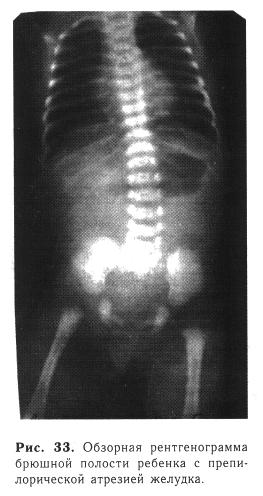

Рентгенологическое исследование — один из основных методов диагностики. На обзорной рентгенограмме брюшной полости при вертикальном положении отмечаются большой газовый пузырь и уровень жидкости, соответствующие растянутому желудку, в петлях кишечника газа нет (рис. 33). Иногда выявляют «немой живот» — отсутствие газа на всем протяжении желудочно-кишечного тракта. При наличии подобной рентгенологической картины другие методы исследования обычно не требуются. Некоторые хирурги предлагают вводить в желудок йодолипол — при атре-зии желудка наблюдается выпячивание пилорической мембраны в просвет двенадцатиперстной кишки.